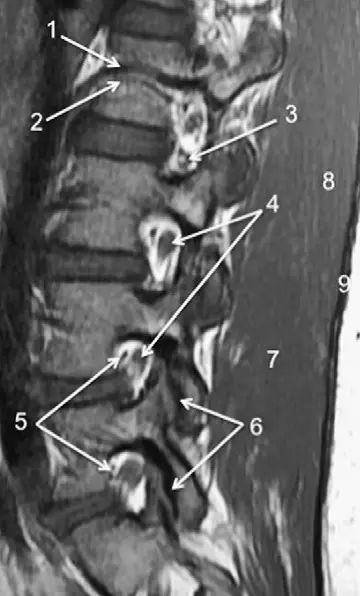

图1正常脊椎的MRI检查,左图为正中矢状位T2WI,右图为T1WI图 2 胸椎 T2WI 轴位图:1,肋椎关节;2,类骨头;3,黄韧带;4,椎弓根;5,椎弓板;6,横突;7,棘突;8,肋横突关节;9,肋结节;10,半奇静脉;11,后纵韧带图 3 腰椎矢状位 T1WI 序列成像:1,脊髓;2,脊髓圆锥;3,马尾;4,蛛网膜下腔;5,硬膜外脂肪;6,黄韧带;7,棘间韧带;8,棘上韧带;9,椎体静脉丛;10,硬膜外静脉丛;11,硬膜外脂肪;12 主动脉图 4 L5/S1 水平轴位 T1WI 序列成像:1,腰肌;2,L5 神经根(前支);3,L5 神经根(后支);4,黄韧带;5,蛛网膜下腔;6,马尾神经根;7,小关节面;8,髂腰韧带;9,左髂外静脉;10,左髂外动脉;11,右髂外动脉;12,右髂外静脉;13,多裂肌;14,竖脊肌组图 5 腰椎旁矢状位 T1WI 序列成像:1,腰静脉;2,腰动脉;3,椎间孔静脉;4,脊神经节后根;5,椎间孔静脉;6,关节面;7,多裂肌;8,竖脊肌群;9,胸腰筋膜,后层图 6 胸椎 T1WI 序列成像:1,胸髓;2,蛛网膜下腔;3,硬膜外脂肪;4,黄韧带;5,多裂肌;6,棘突;7,硬膜外静脉;8,棘上韧带图 7 胸椎矢状位 T2WI 序列成像:1,胸髓;2,蛛网膜下腔;3,黄韧带;4,多裂肌;5,棘突;6,棘上韧带;7,椎体静脉;8,脊髓圆锥;9,马尾图 8 胸椎旁矢状位 T2WI 序列成像:1,硬膜囊后壁;2,硬膜外脂肪;3,黄韧带图 9 胸椎轴位 T2WI 序列成像:1,主动脉;2,半奇静脉;3,奇静脉;4,椎间孔静脉;5,胸肋间血管;6,脊神经节后根;7,椎体静脉;8,后纵韧带;9,脑脊液流动伪影;10,多裂肌;11,背最长肌;12,斜方肌图10 胸椎旁矢状位 T2WI 序列成像:1,椎间孔静脉;2,胸椎旁肋间动静脉;3,神经根;4,上关节突;5,下关节突;6,关节面;7,椎弓峡部;8,椎弓根;9,黄韧带;10,竖脊肌群;11,斜方肌——本期完——